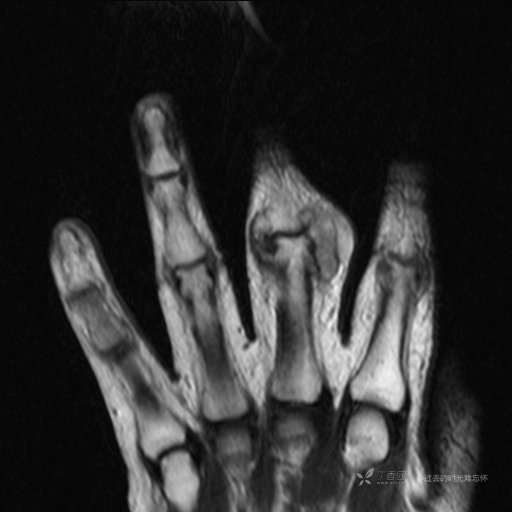

患者性别:女

患者年龄:59岁

主诉: 手指肿胀2年,其间明显肿胀,抗炎后肿胀减轻,近几日肿胀疼痛加重。

T2及T2压脂